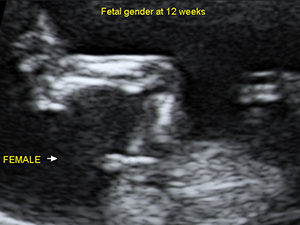

女性

懷孕20週的女性胎兒性器官(箭咀)